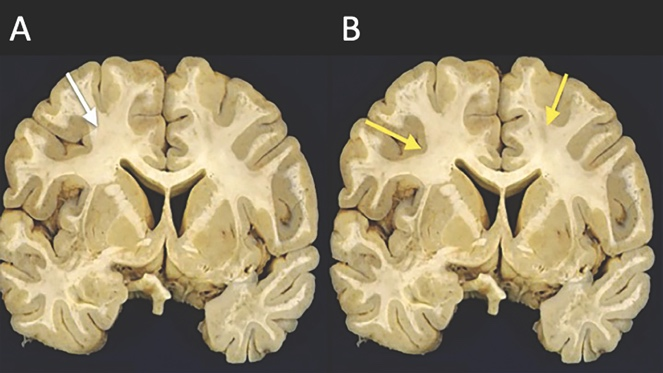

Imagen demostrativa del abordaje transcortical (A) y transulcal (B) para lesiones subcorticales. El abordaje transulcal acorta la distancia entre la corteza y la lesión y reduce la posibilidad de complicaciones cuando un cavernoma se encuentra en áreas elocuentes.